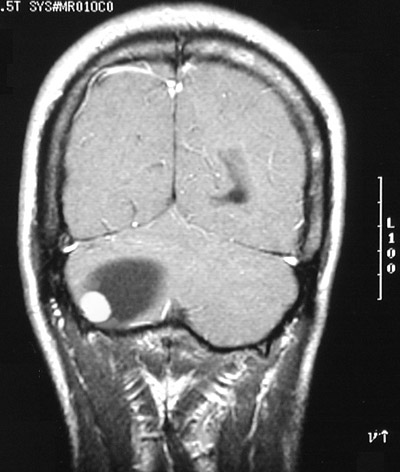

| This enhanced MRI scan in coronal view demonstrates a cystic mass with a brightly enhancing mural nodule. This is a cerebellar hemangioblastoma. Polycythemia is a paraneoplastic syndrome that can be due to these tumors. Polycythemia occurs in about 10% of patients with hemangioblastoma and is due to the production of erythropoietin by the tumor. |